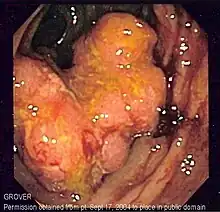

Endoscopy

A colonoscopy is the best test for making the diagnosis of Crohn's disease, as it allows direct visualization of the colon and the terminal ileum, identifying the pattern of disease involvement. On occasion, the colonoscopy can travel past the terminal ileum, but it varies from person to person. During the procedure, the gastroenterologist can also perform a biopsy, taking small samples of tissue for laboratory analysis, which may help confirm a diagnosis. As 30% of Crohn's disease involves only the ileum,[1] cannulation of the terminal ileum is required in making the diagnosis. Finding a patchy distribution of disease, with involvement of the colon or ileum, but not the rectum, is suggestive of Crohn's disease, as are other endoscopic stigmata.[134] The utility of capsule endoscopy for this, however, is still uncertain.[135] A "cobblestone"-like appearance is seen in approximately 40% of cases of Crohn's disease upon colonoscopy, representing areas of ulceration separated by narrow areas of healthy tissue.